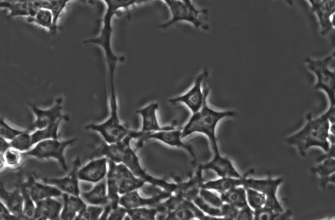

Процесс создания модельных организмов или клеточных линий, имитирующих болезни, является ключевым этапом в исследовании нейродегенеративных заболеваний. С помощью современных методов редактирования можно вносить именно те мутации, которые встречаются у больных людей, что позволяет воссоздать патологические особенности в лабораторных условиях.

| Клеточные модели | Используются нейроны, полученные из стволовых клеток. | Быстрые и недорогие; позволяют моделировать отдельные аспекты заболевания. | Не отражают полную сложность организма. |